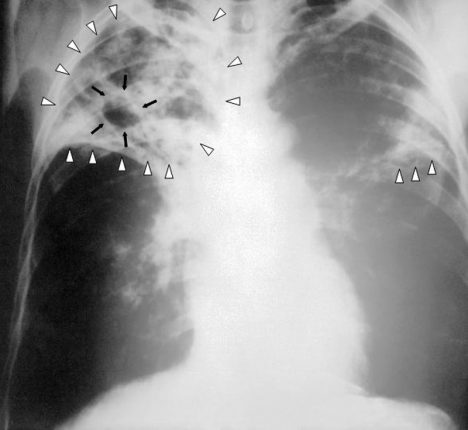

Tuberkulóza (TBC) neboli ftíza, souchotiny či úbytě jsou chronickou infekční chorobou, jejíž první známky byly zjištěny již na pozůstatcích bizona starého zhruba 18 000 let! Za nejstarší druh TBC bakterií je považováno Mycobacterium tuberculosis.

Jde o jednu z nejagresivnějších nemocí vůbec. Napadá nejen dýchací, ale také nervovou soustavu. Neblaze ovlivňuje funkčnost kostí, kloubního aparátu, močové a pohlavní soustavy, střev a dalších částí těla.

V zásadě je schopna zachvátit většinu tělesných orgánů, které jsou imunitně oslabeny. Málokdo tuší, že existuje i oční a ušní forma TBC. Souchotiny neboli TBC byly v 19. a 20. století vnímány jako onemocnění chudých.

V současné době existuje v České republice systém povinných kontrolních hlášení, které jsou součástí Registru TBC. Oproti západním zemím má přitom Česká republika vyšší úmrtnost na tuberkulózu. Jak poznáte, že máte TBC? Symptomy jsou kašel s krvavými hleny, horečka, pocení, bledost a ztráta tělesné hmotnosti.